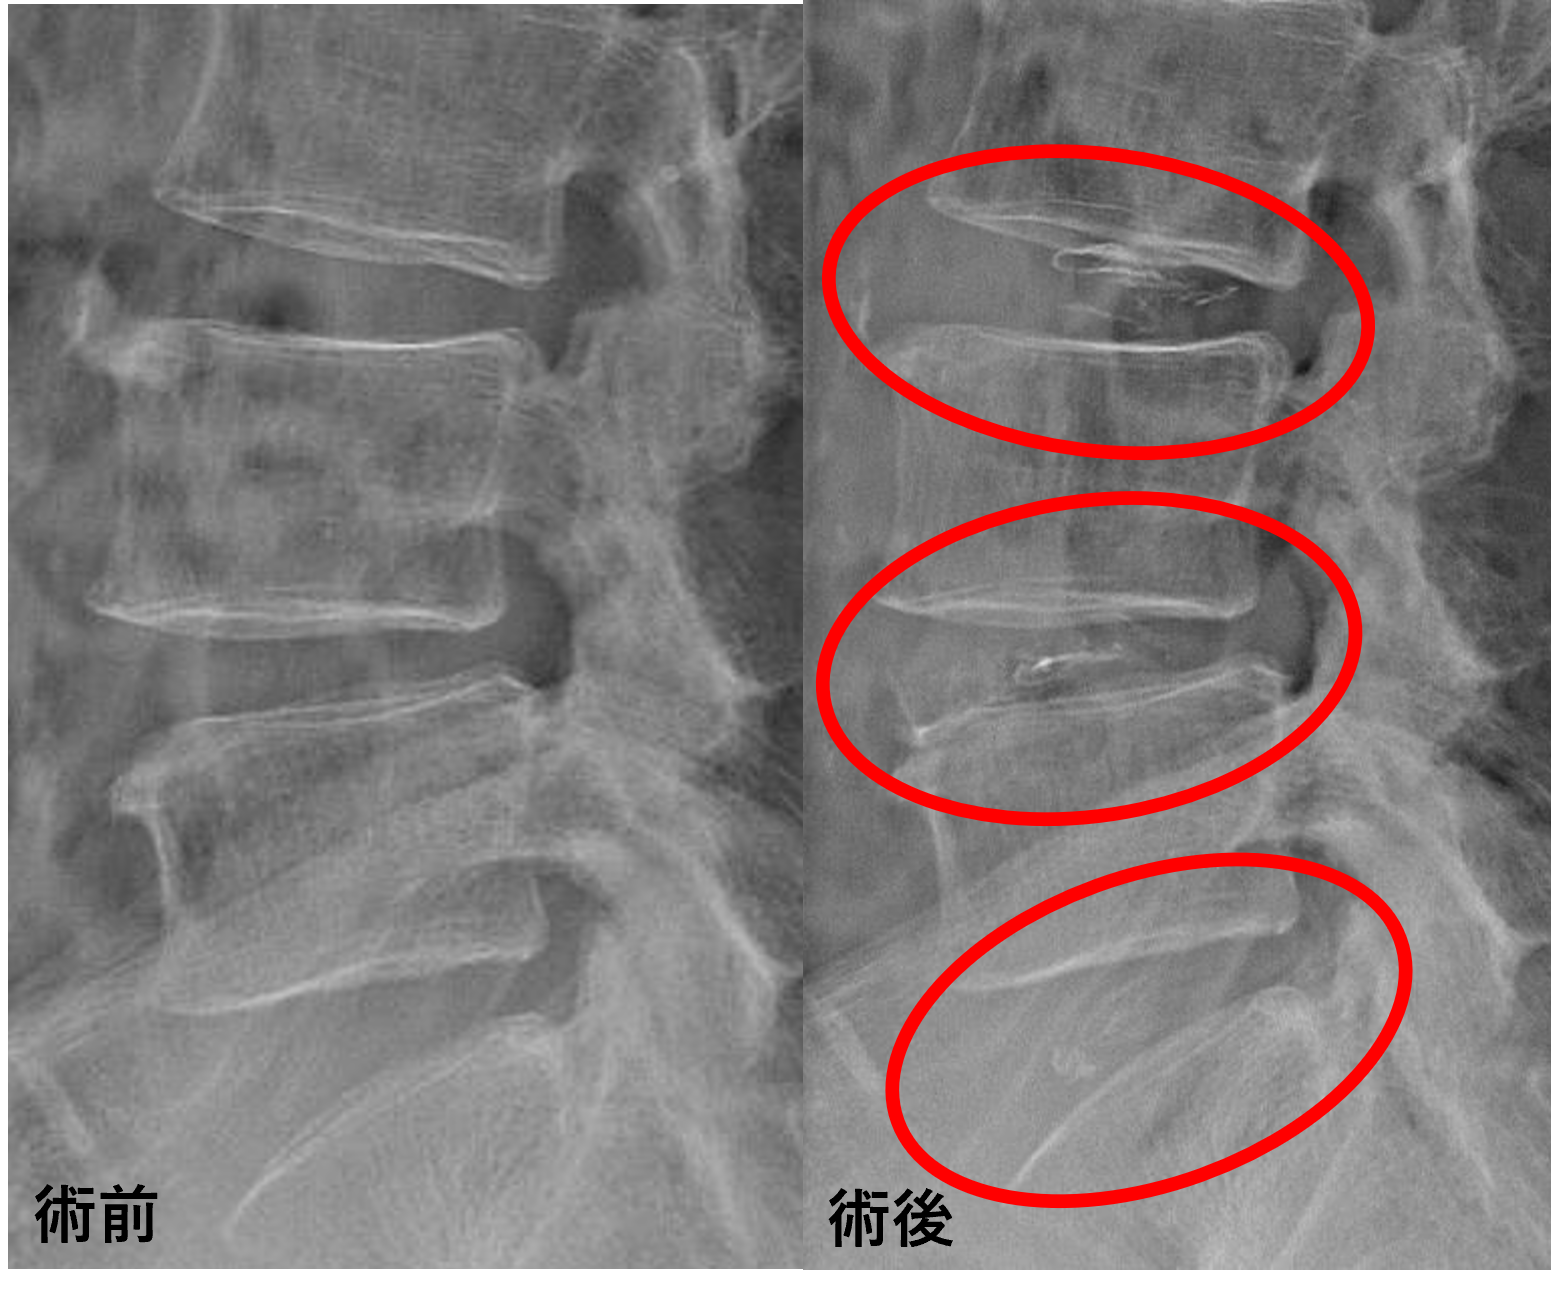

患者様と相談の元、L3/4、4/5、5/sにセルゲル法を施行

治療は小寺院長が行いました。

治療は30分程度で終了

回復室で休憩後、歩いて帰院されました。